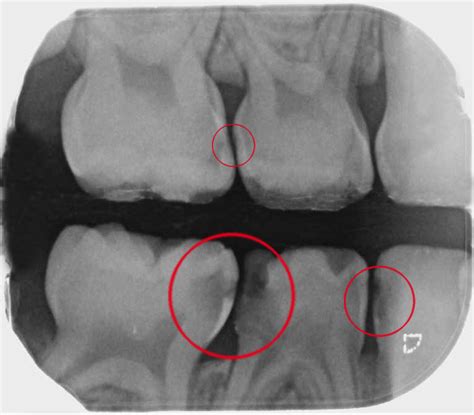

Los errores más frecuentes en el diagnóstico basado en radiografías de aleta de mordida incluyen: tratamiento de tejido duro dentario sano al asumir la existencia de caries dentinaria sin señales visuales de lesión de esmalte; infravaloración de la extensión de las lesiones por caries que abarcan la mitad externa de la dentina; sobrevaloración de la profundidad de las lesiones en la mitad interna del esmalte; y el uso de criterios poco concretos para fundamentar la decisión terapéutica. Estos ejemplos demuestran que las diferencias inter e intrapersonales no son infrecuentes y que a menudo se toman decisiones terapéuticas con un grado de inseguridad.

La clasificación presentada en la tabla 2 se basa en la correlación existente entre el grado de penetración radiográfica de la lesión y la inspección visual de la superficie correspondiente tras la separación temporal del diente. En un estudio, se halló una superficie intacta en todos los casos de caries de esmalte inicial (R1); las lesiones que en la radiografía alcanzaban la mitad interna del esmalte (R2) mostraron clínicamente una cavidad en el 10.5% de los casos. En los casos con una lesión cuya extensión radiográfica alcanzaba la mitad externa del esmalte, el 59% de las superficies permanecían intactas, y solo se pudo asumir con certeza un colapso de la superficie cuando la radiolucidez ocupaba la segunda mitad de la dentina. Por consiguiente, la clasificación existente fue ampliada para incluir precisamente esta categoría (R3a) y utilizada en estudios epidemiológicos para clasificar la profundidad de la lesión y analizar la progresión de la caries interproximal. Esta clasificación ampliada se puede extrapolar a la caries oclusal, aunque con limitaciones. La evaluación de radiografías de aleta de mordida para determinar la presencia de caries oclusal incrementa la sensibilidad del diagnóstico visual, pero solo cuando existe caries de dentina manifiesta y confirmada.

En lesiones de grado R1 y R4, los hallazgos radiográficos permiten confirmar de forma bastante concluyente el diagnóstico clínico de la superficie y la decisión terapéutica, dado que por lo general las intervenciones invasivas solo están indicadas en presencia de cavidad. En las categorías R2, R3a y R3b, el grado de seguridad que ofrecen los hallazgos radiográficos no es tan elevado.

Las áreas radiolúcidas interproximales constatadas en las radiografías de aleta de mordida que penetran de forma clara en la dentina (R3b, R4) deberían tratarse con medidas preventivas y restauradoras dada la alta probabilidad de que se produzca una cavitación de la superficie. En cambio, las lesiones detectables radiográficamente que solo afectan a la dentina tangencialmente (R3a) requieren una evaluación individualizada.